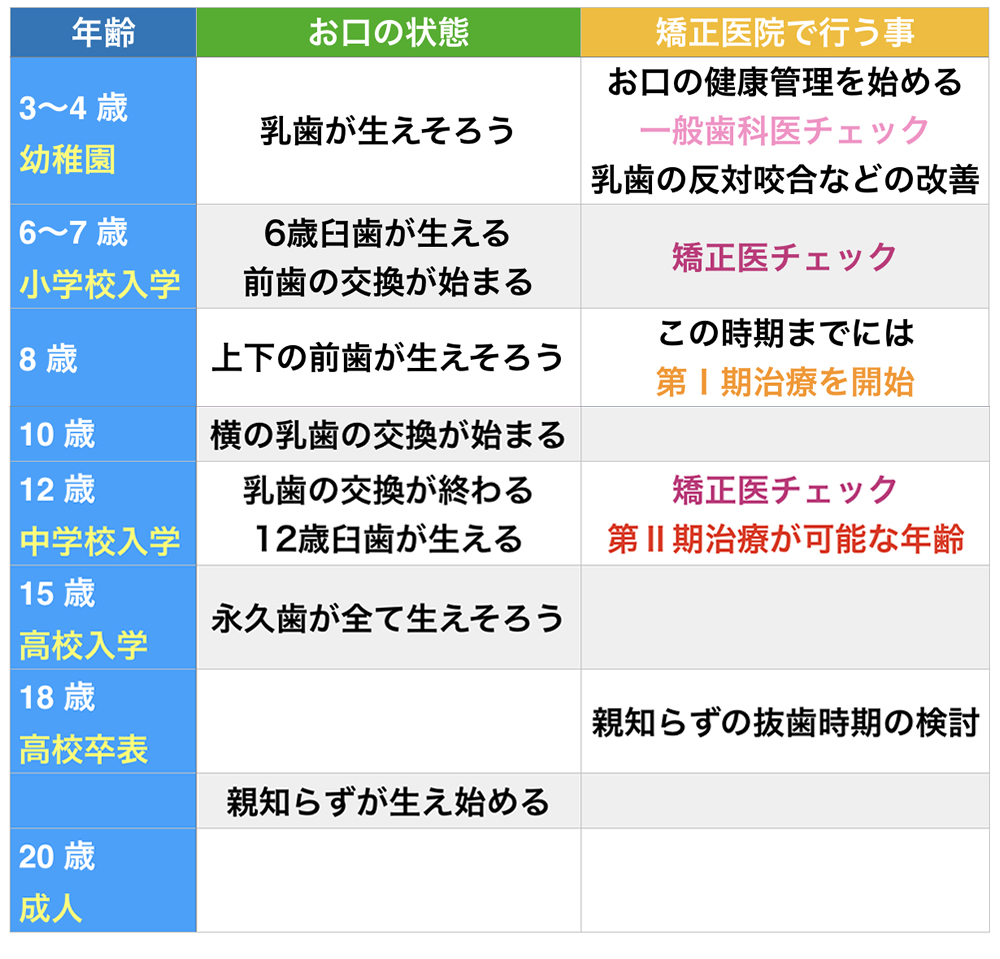

子供の矯正治療は、第 Ⅰ 期治療と 、第 Ⅱ 期治療の2段階で行います。

第 Ⅰ 期治療 6歳までが乳歯列期、6歳になると下の前歯が生え替わり始め混合歯列期に入ります。また、6歳臼歯と言われる、第1大臼歯が生え始めます。6歳~8歳で上と下の前歯が生え揃います。この時期までには、第 Ⅰ 期治療は開始されると良いと思います。 8歳~10歳までは、乳歯から永久歯の交換は行われず、この時期に矯正治療は、行いやすいです。10歳~12歳では、横の乳歯が永久歯への交換時期になります。一般的には、同じ部位なら、下の歯の方が早く生え替わり始めます。また、左右、同時期に生え変わった方が、不正咬合は引き起こしにくいです。 |

第 Ⅱ 期治療 12歳で、第二大臼歯が生え始め、永久歯列の完成となります。 この時期からの矯正治療を第 Ⅱ 期治療と言います。 親知らずは、18歳~30歳で生え始めます。親知らず萌出時には、第二大臼歯を押しながら、萌出してくることが多く、早期に抜歯することも検討する必要があります。 |

子供の矯正開始時期は7~9歳 です。成長を利用した矯正を行えます。

0歳ぐらいまでは、顎の成長が旺盛であり、その成長を利用した治療が可能だからです。12歳を超えると、矯正治療による治療は、主に歯の移動によるものになってしまいます。当院では、手のレントゲンを撮影分析することにより、患者様各々の成長時期を考えた治療を行っていきます。年齢と歯の交換時期と成長の時期は、異なります。